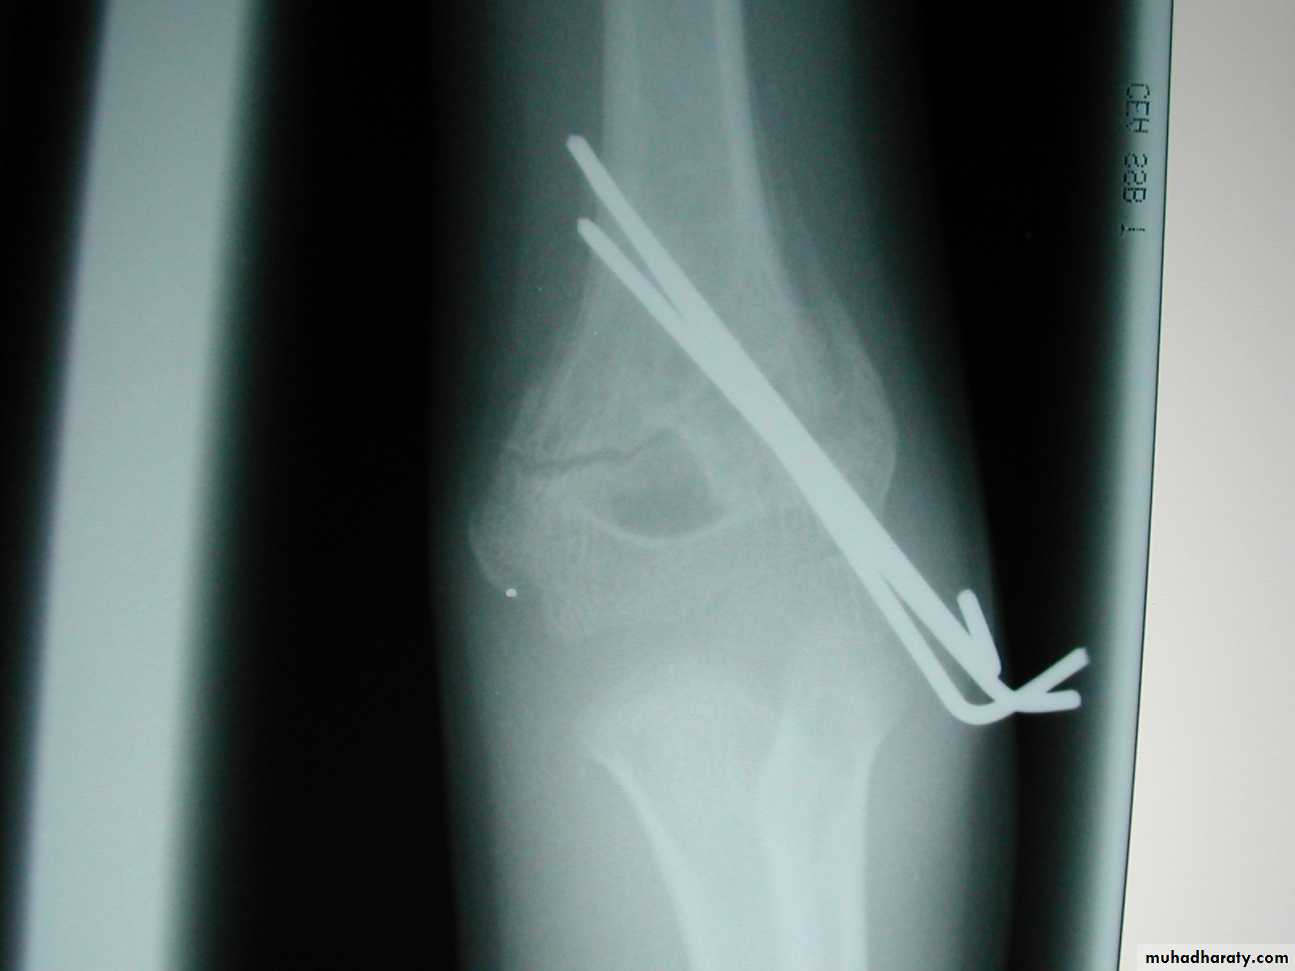

Percutaneous

pin

fixation

If a cast is inadequate,

then what is the standard for maintaining the reduction?

Medial-lateral

pins

In what manner may the pins be used?

Two lateral

pinsPins crossing at the

fracture lack stability

*Cheng J, Lam T, Shen W.

J Orthop Trauma 9:511,1995.

What are the principles of lateral pin fixation?

Loss of rotation of distal fragment

These three pins with

no separation allowed rotation.But, since the coronal alignment has been maintained,

in addition to the shaft condylar angle,this rotational malalignment

is usually ofno clinical significance.

Advantages ?

Almost as strong as medial-lateral pins

Disadvantages?

The larger patients may still have rotational instability,requiring supplementation with a medial pin.

How can the rotational stability with lateral pin be enhanced?

By separating the pins

and adding a third pin.